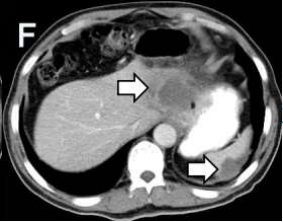

影像檢查

入院完善相關(guān)檢查發(fā)現(xiàn),其肝臟病灶與鄰近胃小彎、膈肌粘連、分界不清;門靜脈左支及肝左靜脈未見顯示,考慮受侵;左上腹腔前側(cè)及后側(cè)腹膜局限性增厚,考慮腹膜轉(zhuǎn)移瘤,部分病灶與鄰近左側(cè)膈肌、脾臟粘連、分界不清。

術(shù)后1周和術(shù)后2月復(fù)查腹部CT均提示:肝臟及左側(cè)腹膜腫瘤可見大片狀低密度壞死區(qū),肝臟腫瘤外周有少許強(qiáng)化灶。心電圖及心肌酶未見明顯異常,腫瘤標(biāo)志物指標(biāo)顯著下降?;颊叩捏w重較術(shù)前上升4kg,疼痛程度及日?;顒?dòng)能力較前明顯改善。

術(shù)后復(fù)查:左為術(shù)后1周,右為術(shù)后2月